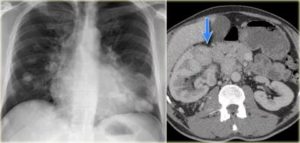

Метастатическим или вторичным раком легких называются опухоли, которым дают начало раковые клетки, попавшие в легочную ткань из других органов.

Метастазы в лёгких бывают разными по форме, ее определяют по рентгеновским снимкам:

- Очаговые метастазы, которые на рентгеновском снимке видны образования разного диаметра. Традиционно этот вариант метастазирования считается проявлением менее агрессивной злокачественной опухоли. При небольшом распространении более благоприятно протекают именно очаговые образования. Они как раз считаются преимущественно гематогенными, то есть занесёнными кровью.

- Инфильтративные метастазы, когда опухолевые клетки расползаются по эпителиальной выстилке альвеол, что на рентгенограмме проявляется в виде сетки или разной формы затемнений. Такой вариант традиционно считают вариантом более агрессивной опухоли — агрессивные по течению меланомы и саркомы дают преимущественно очаговые, а не инфильтративные метастазы в лёгких. Эти вторичные проявления относят к лимфогенным.

При подозрении на метастазы в легких прибегают к следующим методам диагностики:

- Рентгенография. Простой и быстрый, но не самый информативный метод диагностики. Обычно на снимках можно увидеть только опухоли размером более 1 см;

- Компьютерная томография. Позволяет обнаружить очаги менее 5 мм. Это недоступно для рентгенографии и МРТ;

При выявлении теней в лёгких, правильно будет сделать компьютерную томографию с введением контрастного вещества. КТ способна выявить очаги меньше 5 мм, что недоступно магнитно-резонансной томографии.